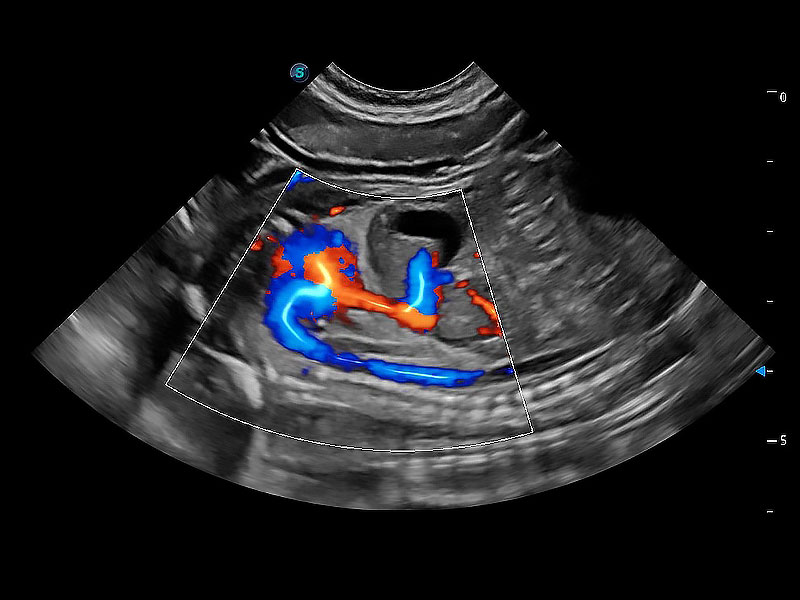

(犬)胎儿主动脉弓立体血流

(犬)胎儿四腔心

(犬)二腔心血流